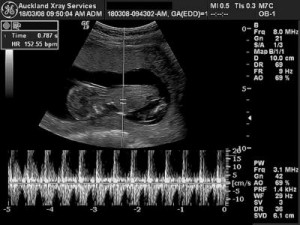

This has been one of the most promising pro-life initiatives. One survey showed that 62 percent of the public thought that abortions shouldn’t be allowed after the evidence of a beating heart. What most people don’t know is just how early that heartbeat can now be detected. With the Doppler device of echograms, there have been readings as early as 6-1/2 to 7 or 8 weeks. And I’m told that by ultrasound, with a vaginal sonogram, the heartbeat can be heard as early as 5 weeks after the last menstrual period, or about 22 days after conception. Which is to say: around the time a woman discovers that she is pregnant.

And yet, the heartbeat itself does not mark the advent of the human life. It is simply part of the development of a human life already in being, generating and integrating its own growth. Nevertheless, if this test of a beating heart offered a new limit on abortions . . . it would be a grand understatement to say that it would have the most dramatic effect on the practice of abortion in this country.

And in fact, on the matter of “viability,” David Forte has pointed out that the fetal heartbeat is one of the strongest predictors of viability: “absent some external, unexpected development, once a fetus has reached the stage of five or six weeks and [the] heart has begun to function, it is almost certain that he or she will continue to develop to full term.”